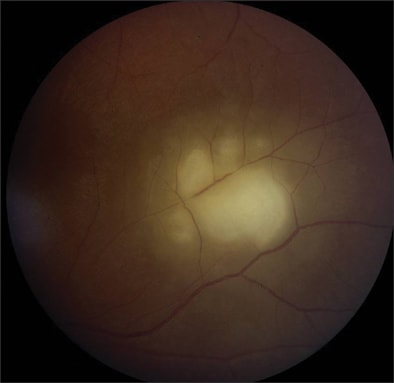

Within the eye, tissue cyst rupture can cause an active focal necrotizing retinitis followed by scar formation.100 This may be directly due to parasitic proliferation, while overlying effects such as vitritis and anterior uveitis may be due to a hypersensitivity response.101 Active lesions are identified as localized areas of infiltrate (Figure 4). Classically, these active lesions are adjacent to old inactive scars and focal vasculitis. The 3 morphological variants of these lesions are large destructive lesions, punctate inner retinal lesions, and punctate outer retinal lesions.102 Secondary complications, such as cataract, glaucoma, cystoid macular edema, and chorioretinal vascular anastomoses, can occur. A minority of patients may have toxoplasmic papillitis, where the foci of inflammation are adjacent to the optic nerve head.103

Figure 4. Toxoplasma gondii retinochoroiditis. Notice the well-circumscribed area of retinochoroidal edema.